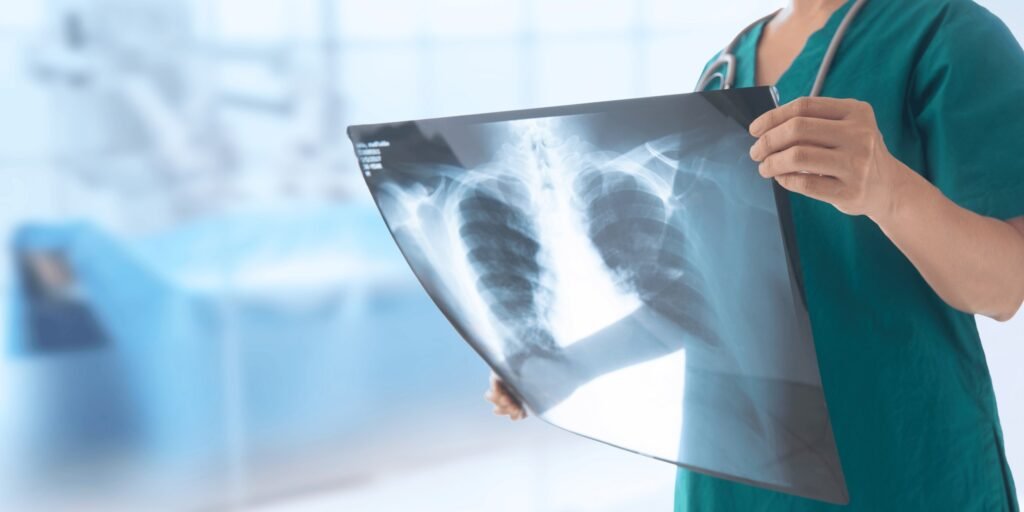

Fast, accurate digital X-ray imaging for fractures, chest diagnoses, and routine radiographic needs — low radiation, quick results.

A digital X-ray captures high-resolution images of bones and chest structures using minimal radiation. These images help diagnose fractures, infections, and lung conditions.

Assess chest infections, lung conditions, and heart silhouette